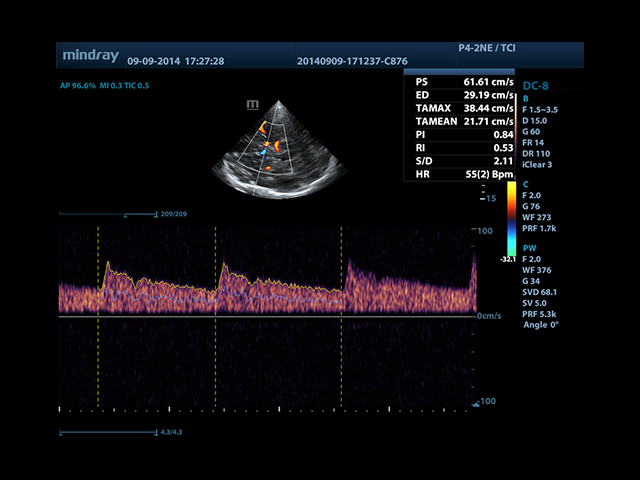

• Smart Doppler - автоматическая подстройка расположения рамки цветового доплера и контрольного объема импульсно-волнового доплера нажатием кнопки.

• Импульсный допплер и HPRF

• Автоматическая трассировка допплеровского спектра с расчетом параметров и индексов

• Smart Doppler™ - автоматическая подстройка расположения рамки цветового допплера и контрольного объема импульсно-волнового допплера